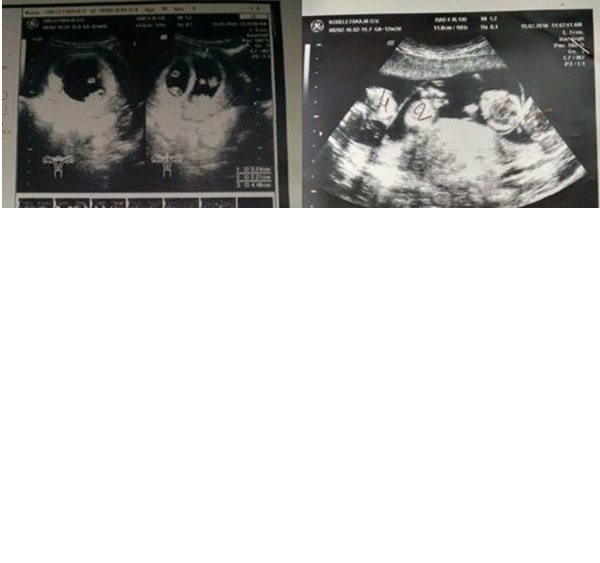

At the point when Oksana went to her ultrasound, she saw the specialist begin to grimace.

Furthermore, soon she got some fantastic news.

“At the point when I saw the shock on the specialist’s face, my heart halted briefly,” Oksana says, and proceeds:

“Then I heard him mutter something as per: ‘You have the right to have a major house by the ocean… ‘”

Then the specialist made sense of: “I can see five embryos, perhaps six. It’s difficult to tell.”

It turns out Oksana was anticipating five children.